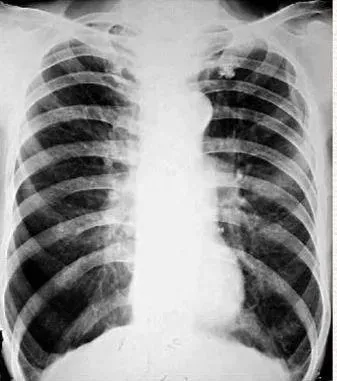

之前見過一個患者60多歲,是嚴重的肺氣腫患者,他的胸廓前後徑和左右徑都已經基本相等,整個胸呈現出圓桶狀,在醫學上,我們稱其為“桶狀胸”。

一旦出現桶狀胸,如果不是外力作用影響,那麼是重度肺氣腫的可能性就很大。

這類患者做檢查,一般都表現為呼吸運動很弱,語音震顫也減弱,叩診清音,呼吸音減弱,有時還會聽到幹、溼囉音。